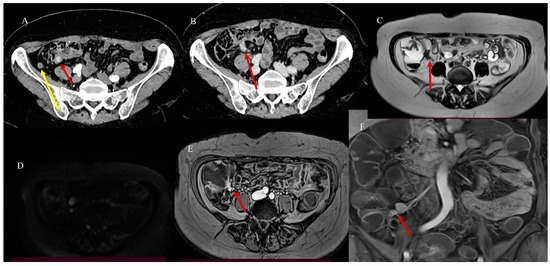

2.7. Metastatic Presentation of Small Bowel Tumors

- Attiyeh, M.A.; Malhotra, G.K.; Li, D.; Manoukian, S.B.; Motarjem, P.M.; Singh, G. Defining MRI Superiority over CT for Colorectal and Neuroendocrine Liver Metastases. Cancers 2023, 15, 5109. [Google Scholar] [CrossRef]

- Shenoy-Bhangle, A.; Baliyan, V.; Kordbacheh, H.; Guimaraes, A.R.; Kambadakone, A. Diffusion weighted magnetic resonance imaging of liver: Principles, clinical applications and recent updates. World J. Hepatol. 2017, 9, 1081. [Google Scholar] [CrossRef]

| MRE | For SBT tissue characterization in non-emergency cases or in stable patients | Intestinal distension with oral biphasic contrast agents, with an optimal volume of 1000–1500 mL that can be ingested over 45–60 min before the examination; T2 HASTE with and without FS on axial and coronal plane; Trufi T2 on axial and coronal plane; DWI; VIBE T1 FS pre-contrast on coronal plane; if stenosis is present, it may be helpful to use the cine-balanced sequence | Tissue characterization through multiparametric sequence; DWI can be used to predict and monitor SBTs; DWI is more sensitive to detecting LI metastasis in liver steatosis | Claustrophobia; PMK not MRI-compatible |